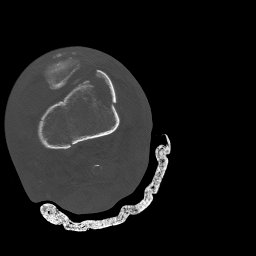

Return to Femoral Shaft Fracture